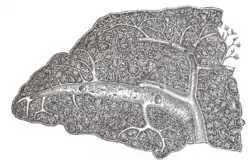

Transverse section of the human spleen, showing the distribution of the splenic artery and its branches | |

The lienal artery is remarkable for its large size in proportion to the size of the organ, and also for its tortuous course. It divides into six or more branches, which enter the hilum of the spleen and ramify throughout its substance, receiving sheaths from an involution of the external fibrous tissue.

Similar sheaths also invest the nerves and veins.

Each branch runs in the transverse axis of the organ, from within outward, diminishing in size during its transit, and giving off in its passage smaller branches, some of which pass to the anterior, others to the posterior part.

These ultimately leave the trabecular sheaths, and terminate in the proper substance of the spleen in small tufts or pencils of minute arterioles, which open into the interstices of the reticulum formed by the branched sustentacular cells.

Each of the larger branches of the artery supplies chiefly that region of the organ in which the branch ramifies, having no anastomosis with the majority of the other branches.